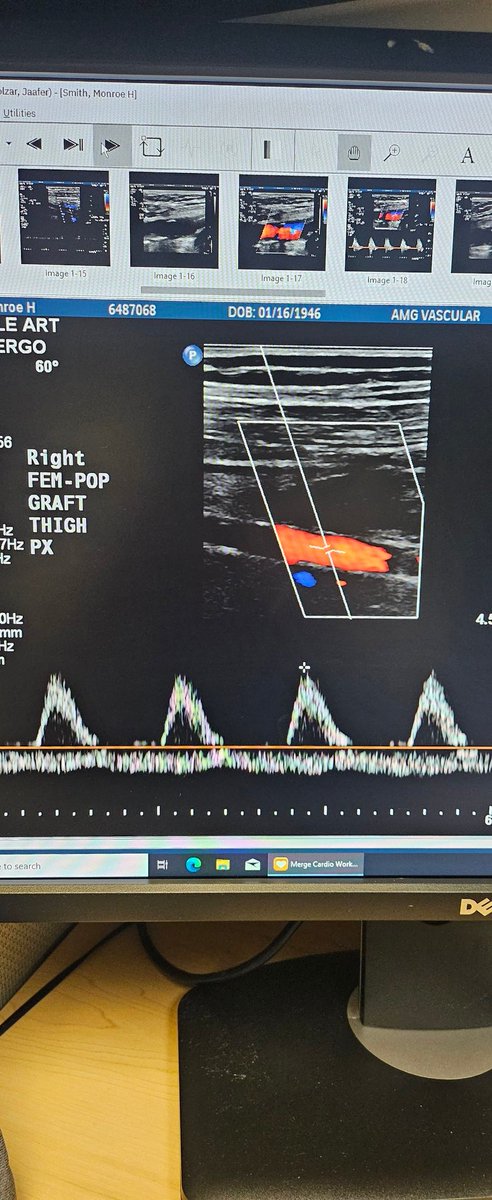

First glimpse of #PTAB w #Detour @endologix 3 week surveillance arterial duplex @ShawnPenn33 @DeanFerreraDO @MarcoShaker @kymbee @tlevin

1

5

10